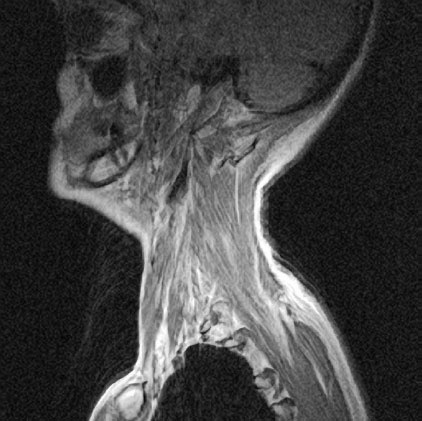

Рисунок 20. Мышцы боковой поверхности шеи и головы способны стимулировать шейные позвонки практически во всех мыслимых направлениях.